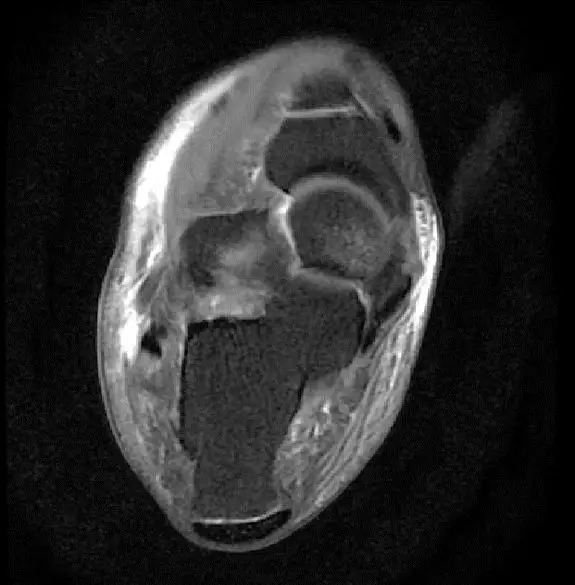

此片可以看到距腓前韧带和跟绯韧带有高信号大片的渗出病变,韧带结构松弛,增粗,这个地方可以看到腓骨前韧带的segond骨折块,所以考虑是踝关节外侧副韧带损伤,腓骨腱的segond骨折。